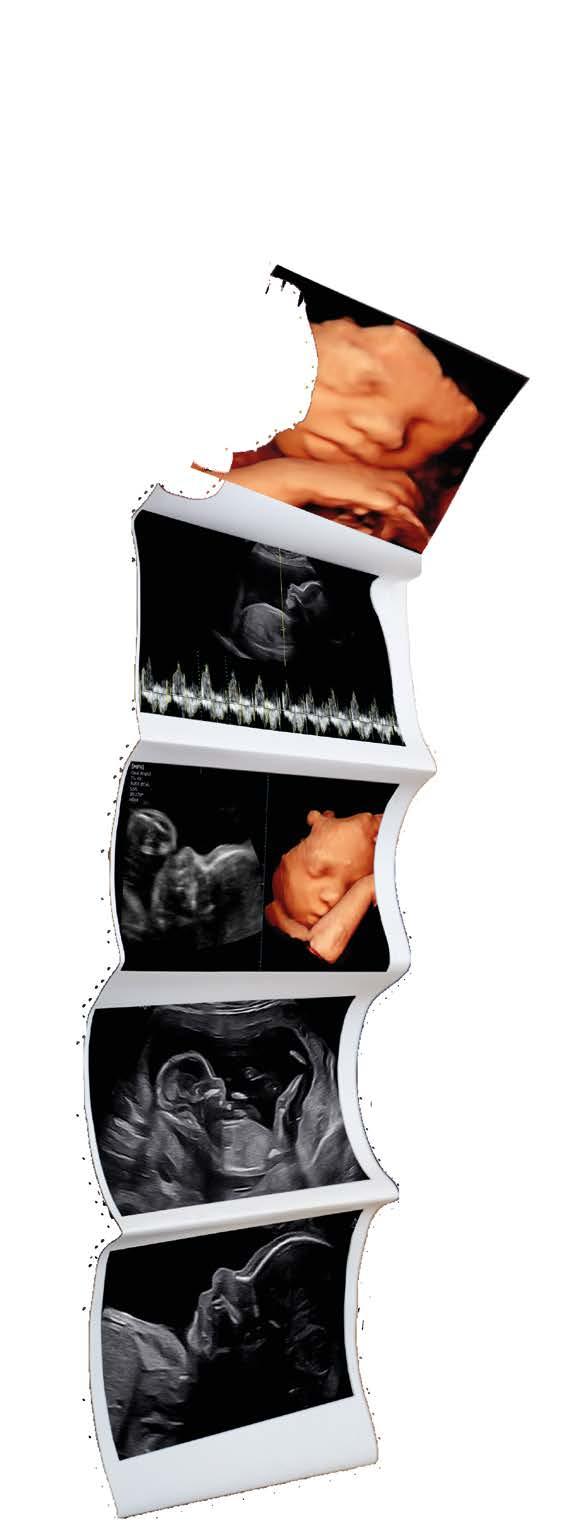

Geslachtsbepaling, 2D, 3D/4D & 6D Pretecho’s

2D Echo en Geslachtsbepaling: Benieuwd naar jullie kleintje?

Kun je niet wachten om te ontdekken of jullie een jongen of een meisje verwachten? Vanaf 14 weken kunnen we met een 2D-echo het geslacht van jullie baby ontdekken. De afspraak duurt tussen 20-30 min, met duidelijke zwart-wit beelden brengen we jullie kleintje in beeld. En als jullie dat willen, onthullen we het geslacht op een manier die bij jullie past. Een speciaal moment dat de zwangerschap tastbaarder maakt en jullie nog meer laat uitkijken naar de komst van jullie kleintje!

Van 3D/4D naar 6D: Een levensechte blik op jullie baby.

Wil je jouw baby écht zien zoals hij of zij eruit zal zien bij de geboorte? Met onze 3D- en 4D-echo’s krijg je al een heel realistisch beeld. Zijn of haar eerste glimlach, een geeuw of een duimpje in de mond. Het is alsof je echt al een glimp opvangt van hoe je kindje er echt uit komt te zien. Als je denkt dat dit realistische is! Dan gaan we nog een stap verder, want dankzij de nieuwste 6D-technologie ontvang je haarscherp en natuurlijk beeld waarin je kindje tot leven komt. Een onvergetelijke ervaring die je voor altijd bij je draagt!

Echo’s spelen een belangrijke rol tijdens de zwangerschap.Ze bieden een uniek kijkje op de ontwikkeling van het kindje in de buik. Er zijn echter twee verschillende soorten echo’s: medische echo’s en pretecho’s. Het is belangrijk om het onderscheid tussen deze twee te kennen, vooral omdat pretecho’s steeds populairder worden.

Pretecho’s: een persoonlijke herinnering

Pretecho’s zijn niet-medische echo’s die je op eigen verzoek kunt laten doen wanneer jij dat wilt. Ze hebben als doel om ouders een extra moment te geven om hun baby te bewonderen, vaak in 2D, 3D of 4D beeld. Deze echo’s kunnen op elk moment in de zwangerschap worden uitgevoerd, maar bieden geen medische informatie over de baby.

Veel ouders kiezen voor een pretecho om achter het geslacht van het kindje te komen of om samen met eventueel aanstaande broertjes/zusjes en opa’s/oma’s de baby in een ontspannen sfeer te bewonderen en herinneringen te maken. De 3D/4D echo is vooral geliefd, omdat deze een gedetailleerd beeld van het gezichtje van de baby geeft. Soms zie je de baby zelfs lachen of gapen! Dit kan helpen om een nog sterkere band met je baby te voelen. Hoewel pretecho’s geen medische functie hebben, kunnen ze bijdragen aan een bijzondere ervaring tijdens de zwangerschap.